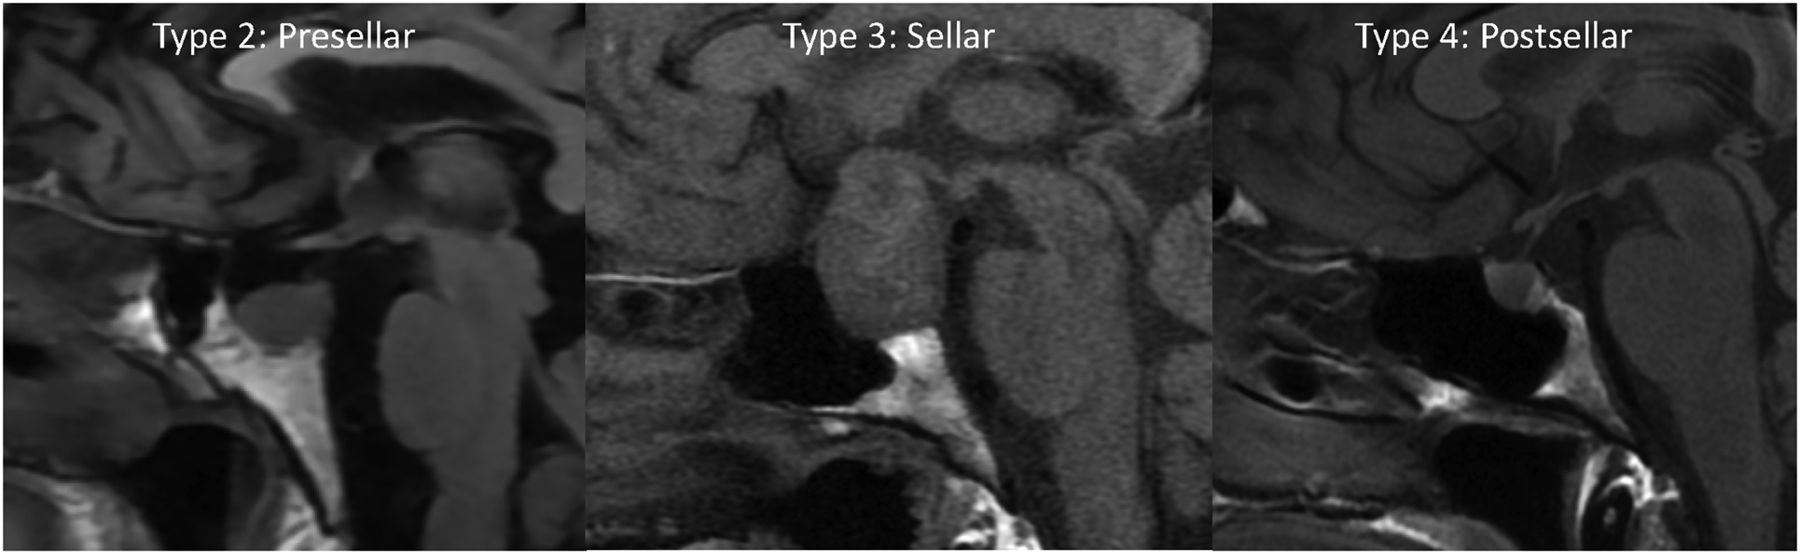

Our internal database was also reviewed for 100 consecutive pathology-proved pituitary adenomas with preoperative MR imaging from January 2021 to January 2022. Images were primarily reviewed for edema and enhancement of the basisphenoid bone marrow. Additionally, the pneumatization pattern of the sphenoid sinus can limit bone marrow evaluation; therefore, the sphenoid sinus pneumatization was evaluated and graded as follows (Fig 1): type 1, conchal; type 2, presellar; type 3, sellar; and type 4, postsellar.13 For the adenoma cases, we measured the maximum diameter and recorded their prolactin levels.

Precontrast T1-weighted sagittal images show the 3 types of sphenoid sinus pneumatization seen in our patients. Type 2 (presellar): the posterior wall of the sphenoid sinus is in front of the anterior wall of the sella turcica; type 3 (sellar): the posterior wall of the sphenoid sinus is between the anterior and posterior wall of the sella turcica; type 4 (postsellar): the posterior wall of the sphenoid sinus is located behind the posterior wall of the sella turcica. An example of type 1 (conchal type, minimal air in the sphenoid sinus) is not shown because this is uncommon and we did not have a patient with this pneumatization pattern.